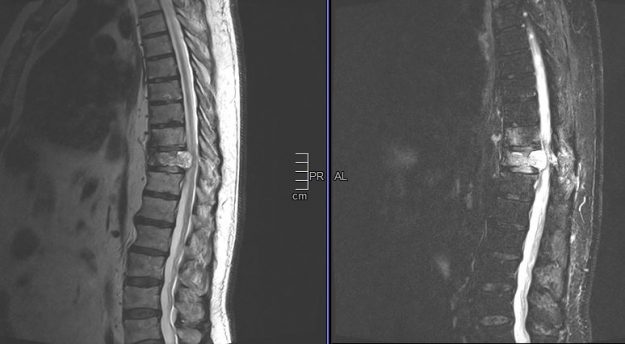

Μετάσταση 10ου Θωρακικού Σπονδύλου (Θ10)

Ασθενής άνδρας 72 ετών με έντονη ραχιαλγία και ιστορικό καρκίνου του πνεύμονα. Ο απεικονιστικός έλεγχος με μαγνητική και αξονική τομογραφία της σπονδυλικής στήλης ανέδειξε μάζα κυρίως στο σώμα του 10ου θωρακικού σπονδύλου (Θ10) με περιβρογχισμό και πίεση επί του νωτιαίου μυελού. (Σημειώστε και τη διήθηση του Θ9 σπονδύλου, χωρίς οστεόλυση). Διενεργήθη αποσυμπίεση του νωτιαίου μυελού…